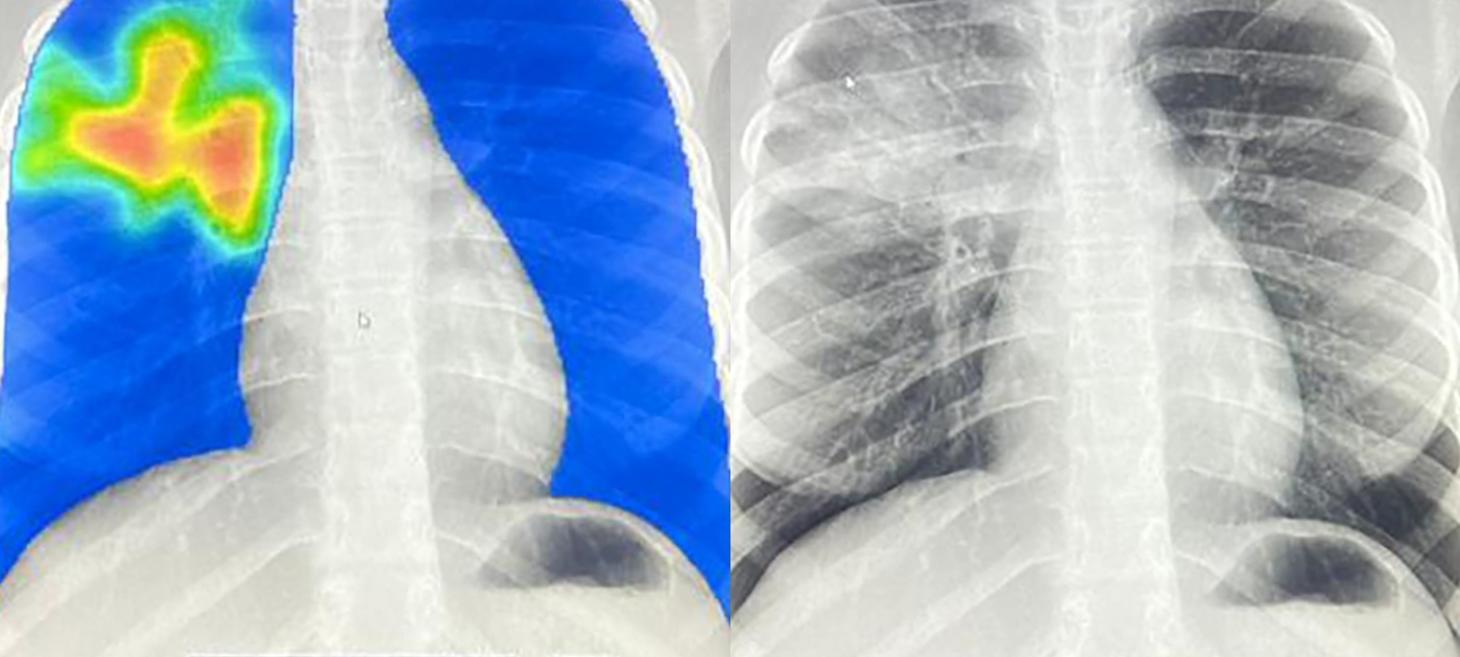

The NPR excerpt examines the deployment of Artificial Intelligence (AI) for tuberculosis (TB) screening in low- and middle-income countries, addressing the urgent challenge posed by a severe shortage of radiologists globally. Organizations champion this technology as revolutionary, noting that mobile X-ray and AI integration allows for rapid diagnosis in hard-to-reach communities and refugee settings, significantly accelerating the diagnostic timeline. For instance, the AI analyzes chest X-rays to pinpoint potential infections, streamlining the overall screening process and reducing the need for traditional sputum samples. However, some professionals caution that the enthusiasm for this solution must be tempered by concerns regarding patient safety and regulatory challenges, as many developing nations lack the necessary legal guardrails to prevent models from making silent errors or deteriorating in performance over time. While acknowledging the clear benefits over having no diagnostic tools, critics emphasize that maintaining accuracy requires complex, costly, multidisciplinary quality control that may undermine the technology’s cheap, simple reputation.